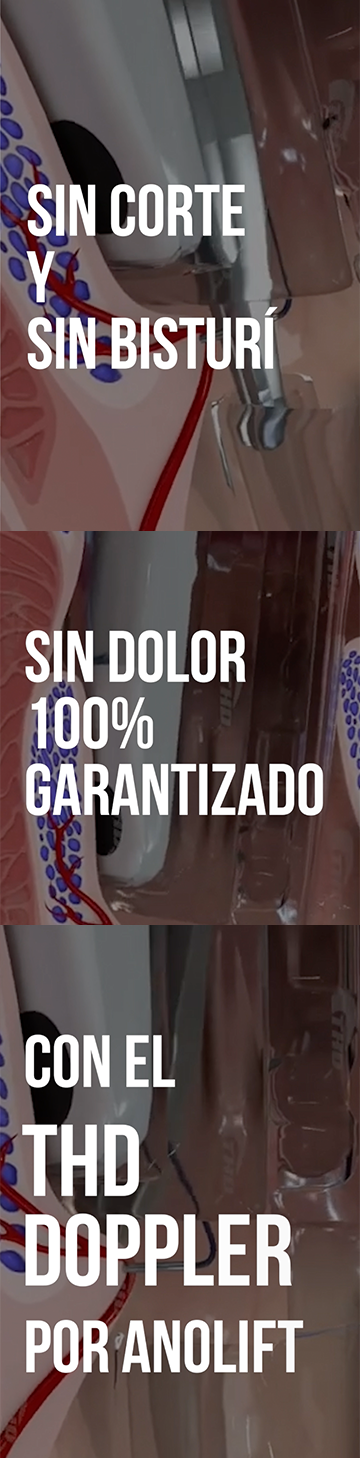

· Enfermedad Hemorroidal